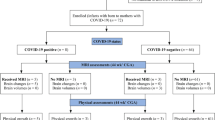

This study was a case–control study, and included newborns diagnosed with COVID-19 in Wuhan, China from January to July 2020. All included newborns had complete neurological evaluations and head magnetic resonance imaging (MRI). The study excluded cases in which family members did not agree to undergo MRI testing. We matched 15 normal neonatal head MRIs at a ratio of 1:3 according to gestational age as normal controls (excluding those with neurological and respiratory diseases), and we compared the brain volumes of different brain regions between the case group and the control group. This study was approved by the hospital ethics committee and complied with the Declaration of Helsinki.

Baseline for confirmation of COVID-19 in newborns

This article included a total of five newborns infected by SARS-CoV-2, including two males and three females. The median gestational age was 39 weeks (range 31–40 weeks). The results of demographic and laboratory examinations of the five neonates with COVID-19 are shown in Table 1. In the infected group, the proportion of elevated procalcitonin and the proportion of characteristic changes in chest fluoroscopy were all higher than that in the control group (P < 0.05).

Evaluation of neurological behavior

On neonatal neurological examination, the median reflex scores were 2 points lower in the infected group than that in the control group (P = 0.0094), and the median orientation and behavior scores were 2.5 points lower in the infected group than in the control group (P = 0.0008). There were also significant differences between the two groups in total scale scores (P = 0.0426). No statistically significant differences were seen between the two groups for the remainder of the comparison (P > 0.05, Table 2). However, the 9-month-old ASQ screening results did not show signs of neurodevelopmental delay, and although neonate 4 had the lowest scores, the scores were still in the normal range (Table 3). These neonates require more prolonged neurodevelopmental follow-up.

Neuroimaging features

Among the five neonates with COVID-19, four neonates presented with WM changes, including two full-term neonates (neonate 1 and neonate 3) who had hypoxic changes. As shown in Supplementary Fig. 2, there are signal changes of varying intensity in the basal ganglia region in T1WI. One neonate (neonate 4) and one full-term neonate (neonate 5) had brain hypoplasia with delayed myelination. MRI of the other neonates with COVID-19 revealed no significant abnormalities.